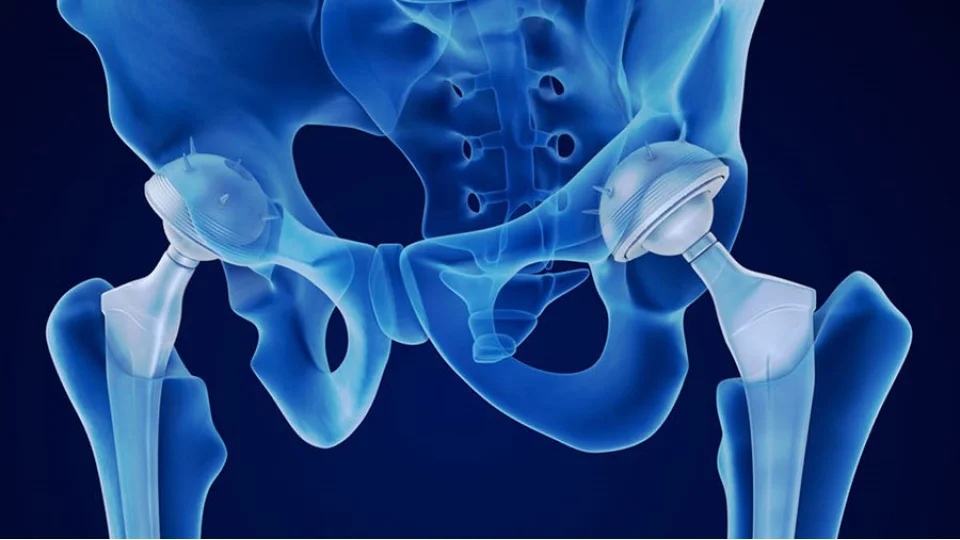

Stanford'lu bilim insanları, 65 milyar dolarlık diz ve kalça protezi endüstrisini adeta yok etmiş olabilir! Yaşlanan kıkırdağı yeniden oluşturmayı ve artriti tersine çevirmeyi sağlayabilecek çığır açıcı bir buluşa imza attılar

50.000 dolarlık bir ameliyattan basit bir hap veya enjeksiyona geçiş artık "ne zaman" olacağı meselesi, "olacak mı" meselesi değil.